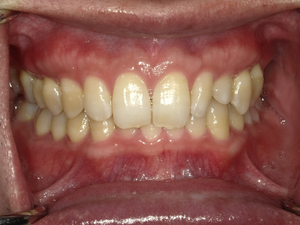

☆before→after☆◯ご相談内容:歯の叢生◯矯正の種類:マウスピース型矯正「インビザラインGO」◯治療期間:10週間◯治療費用:44万円(税込)